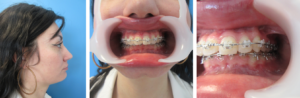

Cette chirurgie s’intègre dans un protocole orthodontico-chirurgical avec la nécessité d’une préparation orthodontique pré opératoire et post opératoire de plusieurs mois.

Il existe une classification pour catégoriser les problèmes d’occlusion dentaire

Classe III : mâchoire du bas trop en avant par rapport à la mâchoire du haut Et/Ou mâchoire du haut en arrière par rapport à la mâchoire du bas